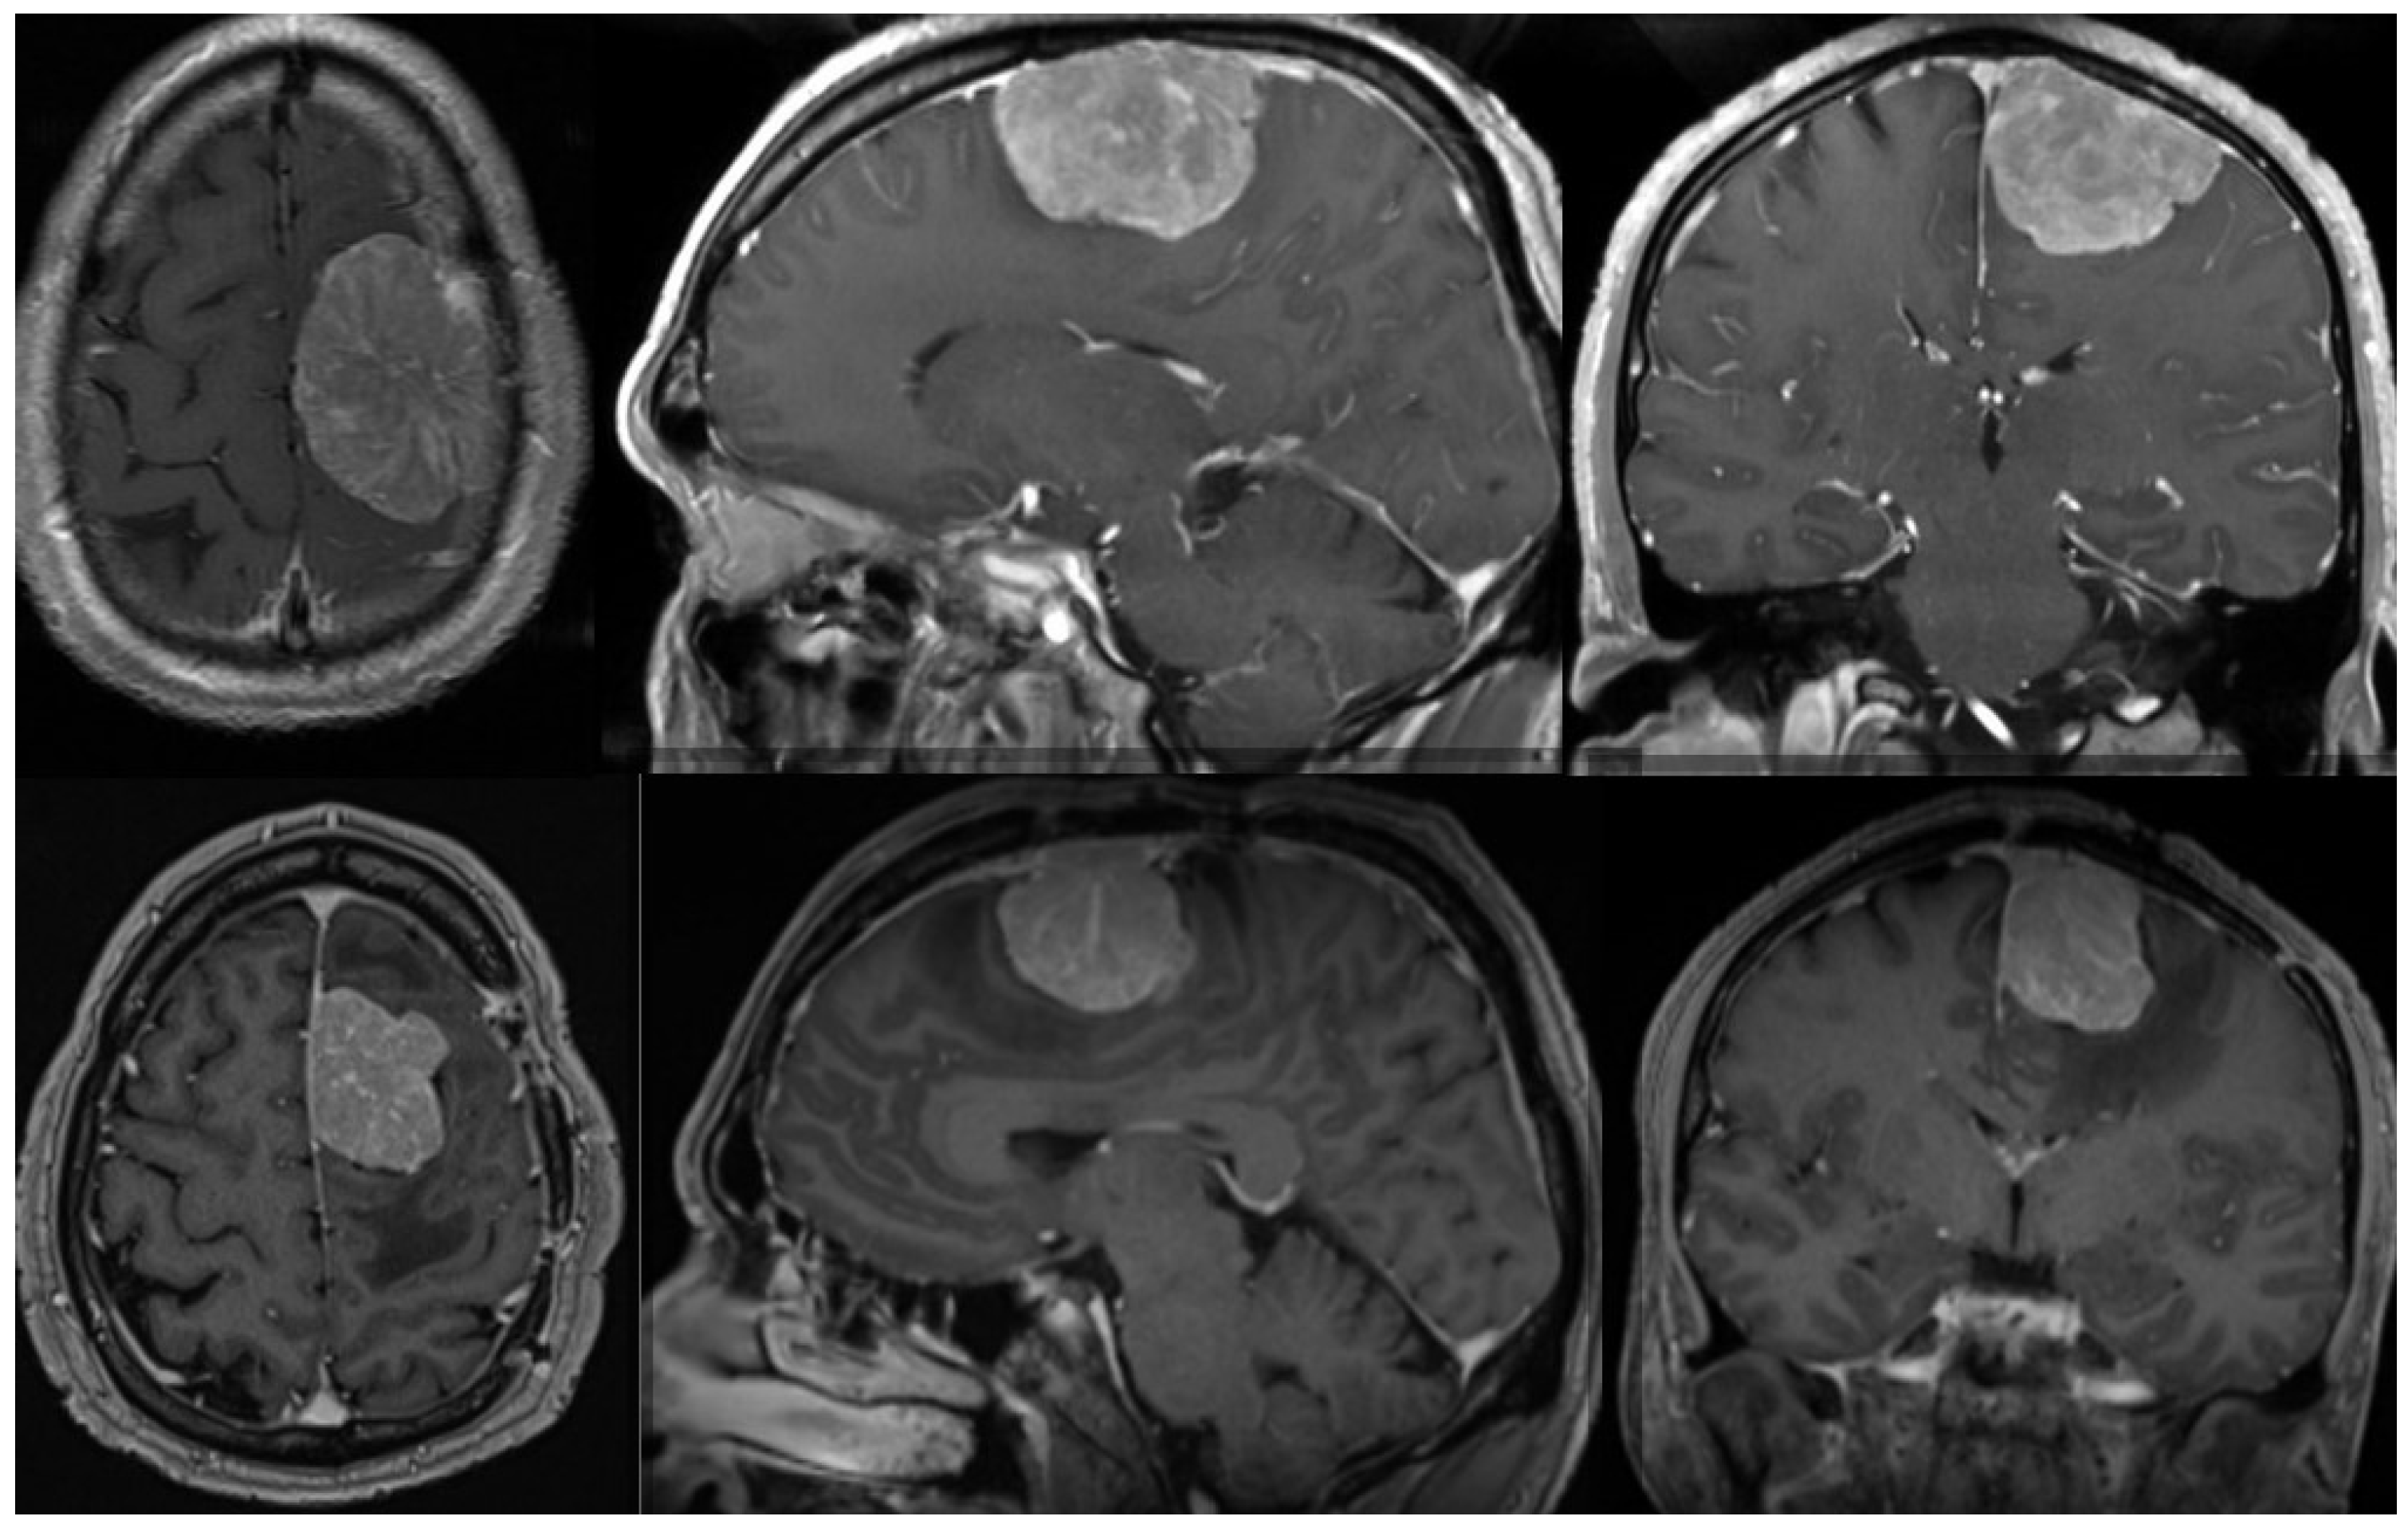

Radiation therapy can be delivered as conventional fractioned photon radiotherapy, stereotactic radiotherapy, stereotactic radiosurgery or fractional stereotactic radiation therapy, intensity-modulated photon radiation therapy, and particle therapy with photons or carbon ions [119,123,132]. External beam radiation therapy is recommended for grade 3 meningiomas, whereas small grade 2 meningiomas can be treated with stereotactic radiosurgery, especially when their diameter is less than 3 cm and they are more than 3 mm from radiosensitive tissues [125,133,134]. In cases of atypical meningiomas with residual tissue, stereotactic radiosurgery is generally used with doses ranging from 12 to 20 Gy [131,135,136]; however, a study conducted by Kano et al. discovered that patients who received less than 20 Gy had a PFS of 29% at 5 years, whereas those who received 20 Gy had a PFS of 63% [135]. In a phase II trial, intensity-modulated photon radiotherapy with doses ranging from 54 to 60 Gy in 30 fractions was administered to patients with incompletely resected atypical meningiomas, which demonstrated that the aforementioned treatment modality was safe and effective and required further research [137]. The administration of particle radiation therapy with either protons or carbon ions enables higher radiation doses, which could improve local tumor control; however, larger prospective studies are still required [138]. Figure 1 shows one example of a patient with an atypical meningioma treated surgically and with radiotherapy.

Figure 1.

Preoperative (upper row) MR of the brain (axial, sagittal, and coronal view after contrast enhancement) showing a 51-year-old male with an atypical meningioma. The patient was operated on and the tumor was removed (Simpson grade 2 resection). The tumor exhibited brain invasiveness and 7 mitotic figures/10 high-power fields. The wall of the superior sagittal sinus, where the tumor was attached, was only coagulated and the sinus was preserved. The patient had no tumor recurrence 3 months after surgery and an 11 mm large recurrence was present after 9 months. (Lower row) The lower row shows the substantial recurrence of the tumor after 15 months. The patient was successfully reoperated on (Simpson grade 2 resection) and received adjuvant radiotherapy on the tumor bed. He had no obvious recurrence three months after the second surgery. The tumor was histologically identical after the second surgery. Genetic analysis was performed after both surgeries, revealing a mutation in the NF2 gene in both cases. No other chromosomal or important genetic abnormalities were detected.